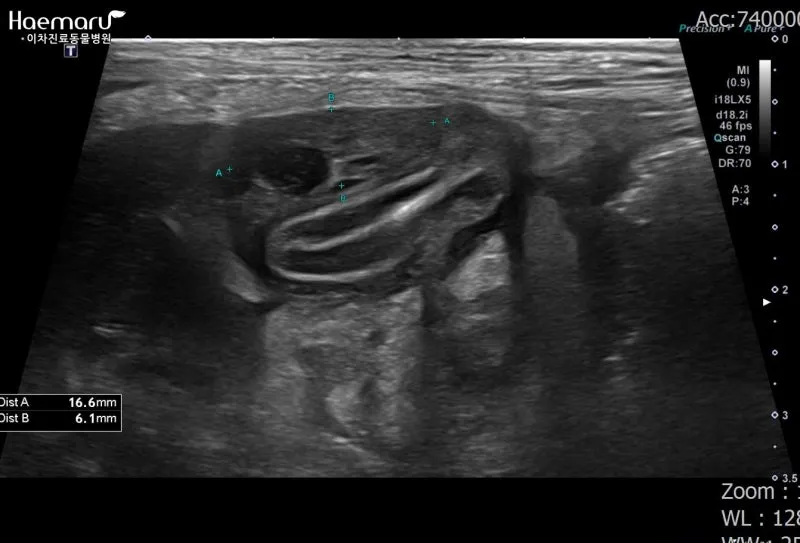

감염성 복막염은 주로 다른 장기의 염증이 확산되면서 발생해요. 예를 들어, 심한 췌장염이나 담낭염이 주변 복막으로 번지는 경우죠. 이런 경우엔 원발 질환 치료와 함께 복막염 관리를 동시에 해야 해서 치료가 더 복잡해집니다.